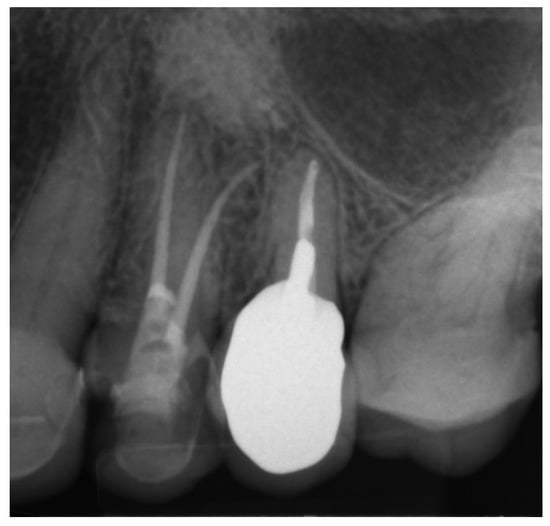

As in the previous case, the virtual drill orientation was established in the centre of the root. The top of the sleeve was 14 mm from the bottom of the tooth chamber. The guide sleeve was 6 mm long and 1 mm in diameter (Figure 26). The template with engraved canal markings was equipped with a window for assessing the correctness of the guide’s intraoral placement (Figure 27). The buccal canal was cautiously negotiated through the guide with a size 10 file (C-Pilot #10) instead of rotated burs. The root canal orifice was reached at a length of 15 mm from the top of the guide sleeve. The time needed to localize the canal path in this case was approximately 10 min. The file was taken to the working length and a conventional root canal treatment followed (Figure 28).

Figure 28. X-ray image showing the correctness of the performed root canal treatment.